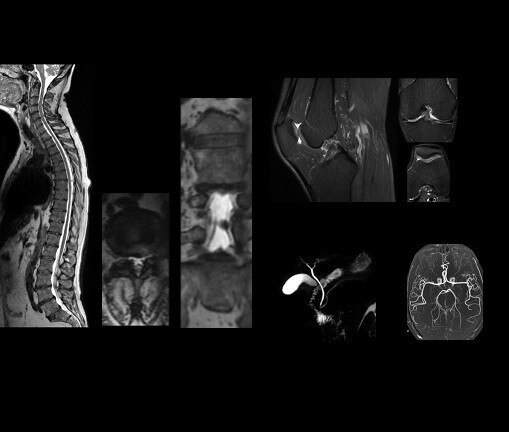

This extensive library of musculoskeletal imaging techniques enables you to image bone, joint and soft tissue with remarkable tissue contrast.

OrthoWorks also includes 3D volumetric Cube with proton-density, combined with ASPIR, which enables improved fat suppression uniformity, which is routinely done as three separate 2D scans. With one 3D acquistion and multi planar reformats, Cubes may replace individual 2D scans.PaedWorks

The four images demonstrate dynamic T1 imaging with PB Navigator, which enables the patient to breathe freely while capturing contrast in fast temporal phases. Whole spine evaluation can be obtained simply with routine T2 frFSE imaging.